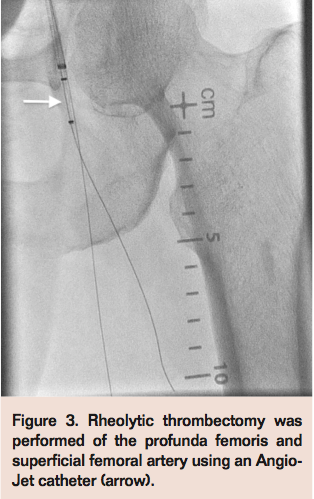

Two days post surgery, he developed new onset left leg parasthesias, discoloration, and pulselessness. Peripheral angiography revealed a left profunda femoris (PF) subtotal occlusion with a hazy filling defect consistent with thrombotic emboli, in addition to ostial 100% superficial femoral artery (SFA) occlusion (Figure 1). Due to recent extensive surgical mitral valve replacement in the setting of endocarditis, followed by infected pacemaker lead extraction, the patient was deemed to be high risk for repeat vascular surgery, and a percutaneous approach to management of septic embolization was pursued.